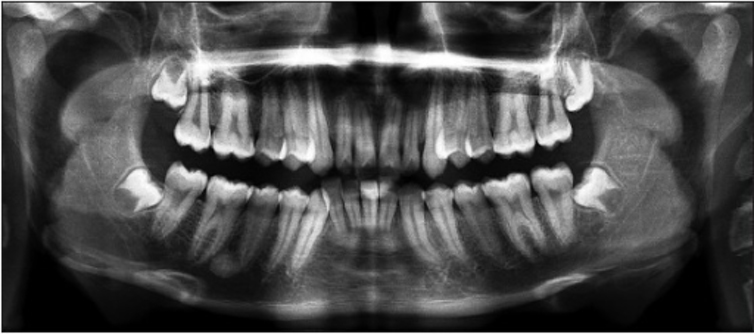

X-ray of a mouth with wisdom teeth emerging on the outside. Journal of Forensic Dental Sciences, CC BY-NC-SA

Teeth and bones can tell something about age – but not someone’s birthday. Journal of Forensic Dental Sciences, CC BY-NC-SA

Sometimes, the estimated age range might include ages below and above 18. Take the development of the wisdom tooth, something we often look at when estimating age of older teenagers and young adults. But the development of this tooth is extremely variable, ranging from never developing at all to erupting anywhere from the mid-teens to early 20s. In such cases, how would a final decision of adult or minor status be made?